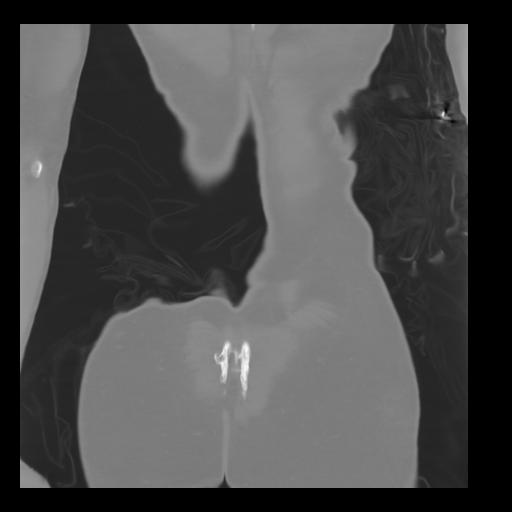

35 CUERPO,CE,Coronal,3.000,CUERPO,Coronal,